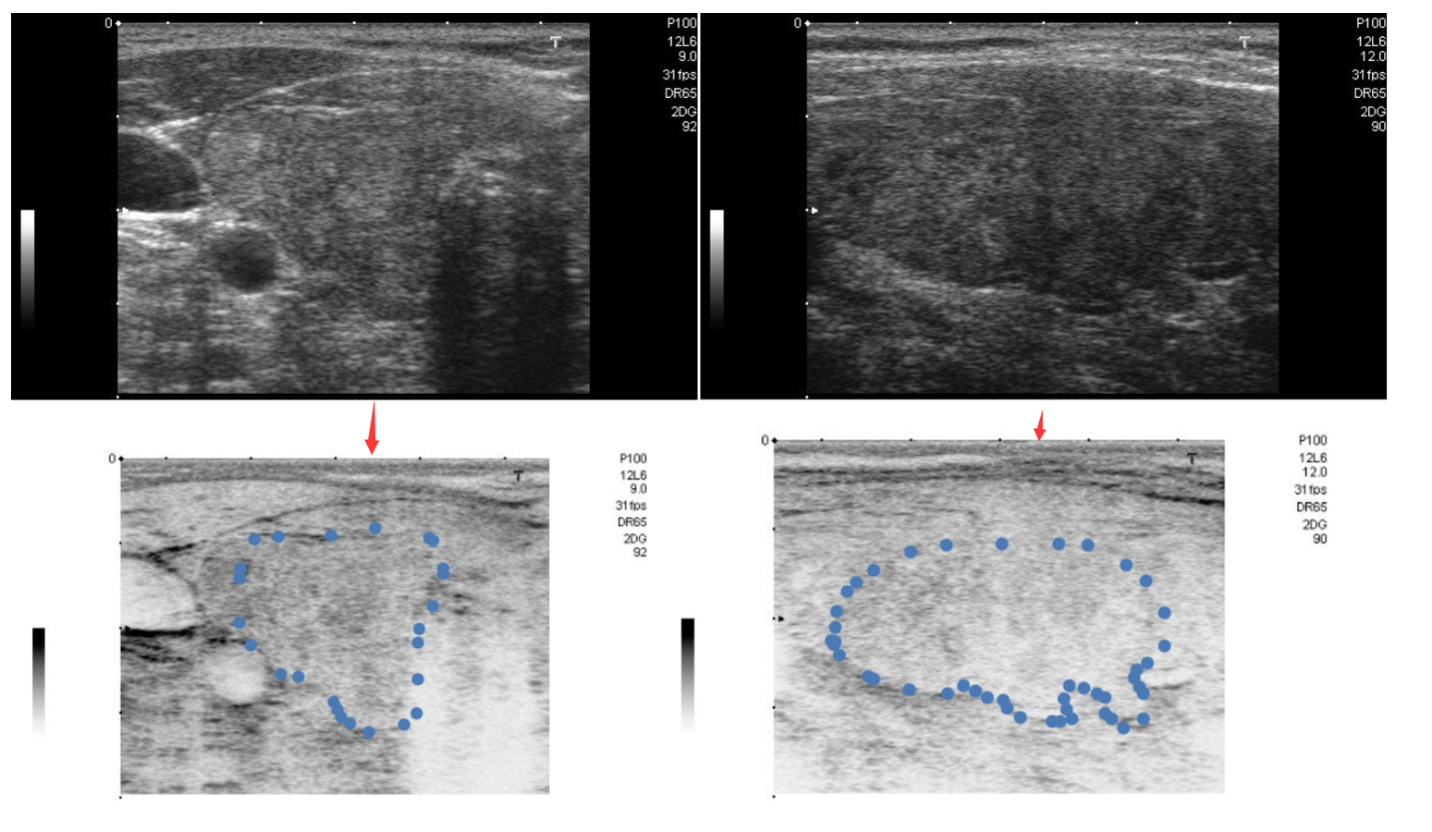

笔记1 甲状腺公共数据下载及预处理对公共数据集进行下载、读取识别和预处理分析 作者:cjg,cjg. 2024-04-12 |

笔记2 甲状腺医院数据预处理对中大五院的医学数据进行处理分析 作者:cjg. 2024-04-12 |